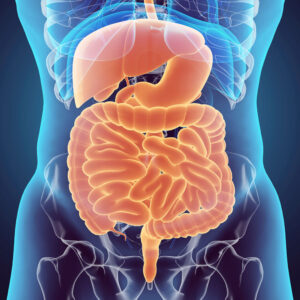

These are being an excellent book on normal home remedies for very common diseases to chronic diseases. It suggests remedies for ailments from head to toe – simple, easy-to-use, and effective.